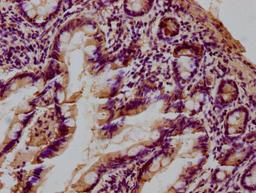

IHC image of CSB-PA012889LA01HU diluted at 1:100 and staining in paraffin-embedded human small intestine tissue performed on a Leica BondTM system. After dewaxing and hydration, antigen retrieval was mediated by high pressure in a citrate buffer (pH 6.0). Section was blocked with 10% normal goat serum 30min at RT. Then primary antibody (1% BSA) was incubated at 4°C overnight. The primary is detected by a biotinylated secondary antibody and visualized using an HRP conjugated SP system.